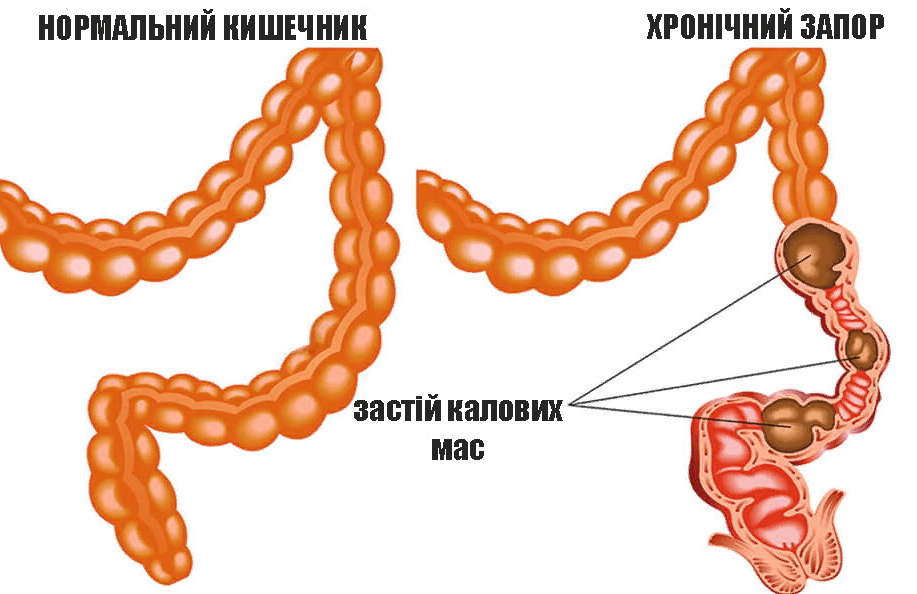

Щоб побачити всю картину, давайте розберемося спочатку, що таке запор.

Запор - це повільне просування фекалій по товстому кишечнику. Зазвичай він асоціюється з великою кількістю сухих, твердих фекалій у висхідній кишці, які накопичуються через надмірне всмоктування рідини. Будь-яка патологія кишечника, яка перешкоджає просуванню кишкового вмісту (виразки або пухлини, спайки, що стискають кишечник), може бути причиною запору.

Іноді запор може бути настільки серйозним, що стискуючі скорочення товстого кишківника відбувається лише 1 раз на кілька днів або навіть 1 раз на тиждень. Це спричиняє накопичуватися величезної кількості фекального матеріалу в товстій кишці, викликаючи збільшення кишки до 7,5-10 см у діаметрі.

Скупчення фекалій викликає тріщини, якими токсини проникають у кров і призводять до серйозної інтоксикації організму.

Внаслідок цього з'являються симптоми інтоксикації: нудота, запаморочення, стрибки артеріального тиску. Тріщини обростають сполучною тканиною, яка у 90% випадків перероджується в Рак.